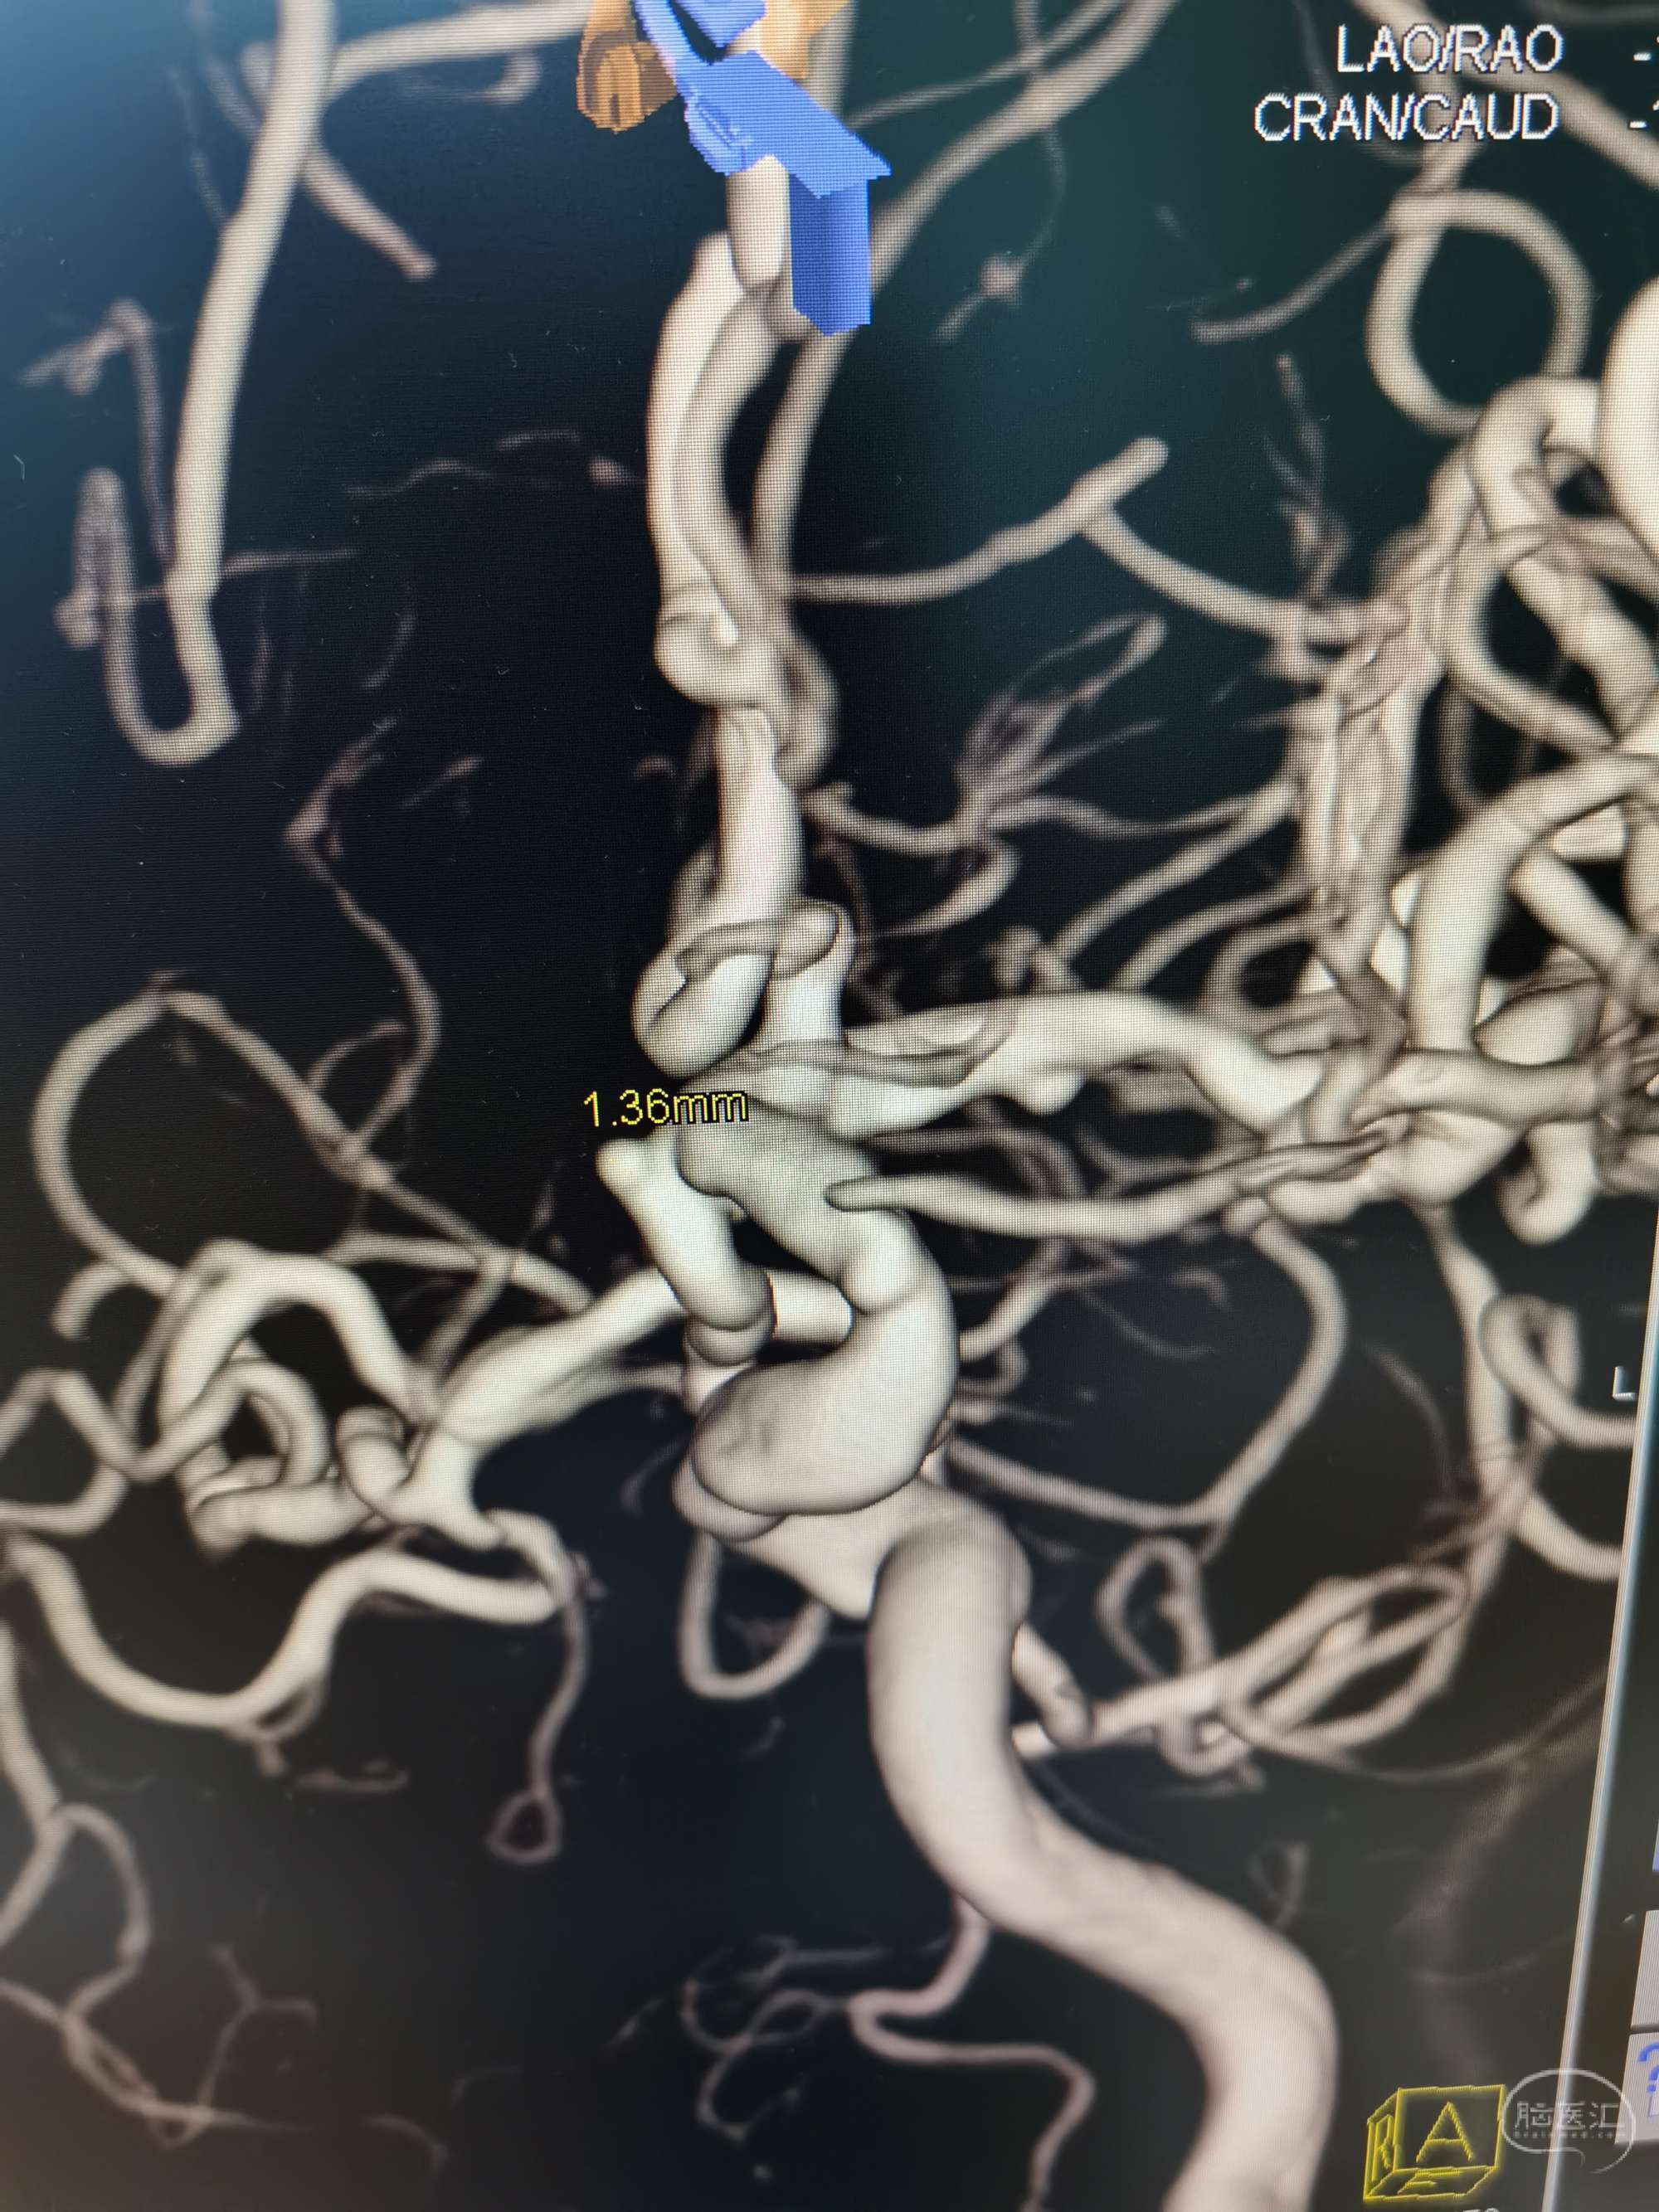

3D示动脉瘤大小约1.36✘1.40mm